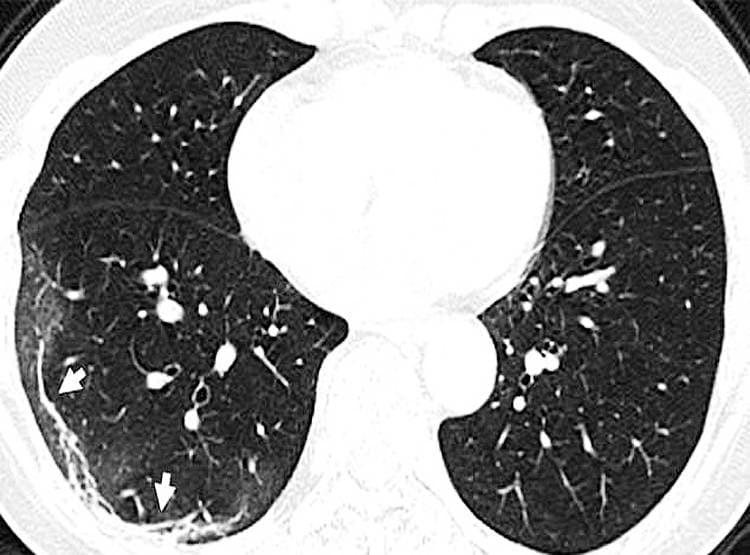

चीन के एक आदमी के फेफड़ों का एक्स-रे किया गया है. इसमें जो तस्वीरें सामने आईं हैं वो बेहद भयानक है. इसमें साफ-साफ दिख रहा है कि कैसे कोरोना वायरस फेफड़ों में घुसकर सांसों को रोकने लगता है. ब्लैक एंड व्हाइट एक्स-रे में आपको ढेर सारे सफेद चकत्ते दिखाई देंगे. एक्स-रे में दिख रहे यही स्पॉट कोरोना वायरस से प्रभावित हिस्सा हैं. यहां बलगम (Mucus) बन रहा है. (फोटोः RSNA)

एक्स-रे को देखने वाले रेडियोलॉजिस्ट इस सफेद चकत्ते को ग्लास ओपेसिटी कहते हैं. यानी फेफड़े में जिस जगह हवा होनी चाहिए, वहां पर कोरोना वायरस विकसित हो चुका है. वह उस स्थान पर बलगम बना रहा है. इसकी वजह से लोगों को सांस लेने में दिक्कत होने लगती है. जिस व्यक्ति का एक्स-रे सामने आया है वह वुहान के मांस बाजार से संक्रमित हुआ था. (फोटोः RSNA)